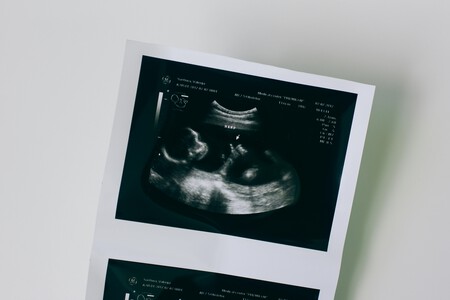

Thaddeus Daniel Pierce llegó al mundo el 26 de julio de 2025 en Ohio, pero su historia comenzó mucho antes: en mayo de 1994, cuando fue concebido mediante fertilización in vitro (FIV). Desde entonces, había estado criopreservado durante más de tres décadas, convirtiéndose en el embrión más viejo en dar lugar a un nacimiento, según MIT Technology Review.